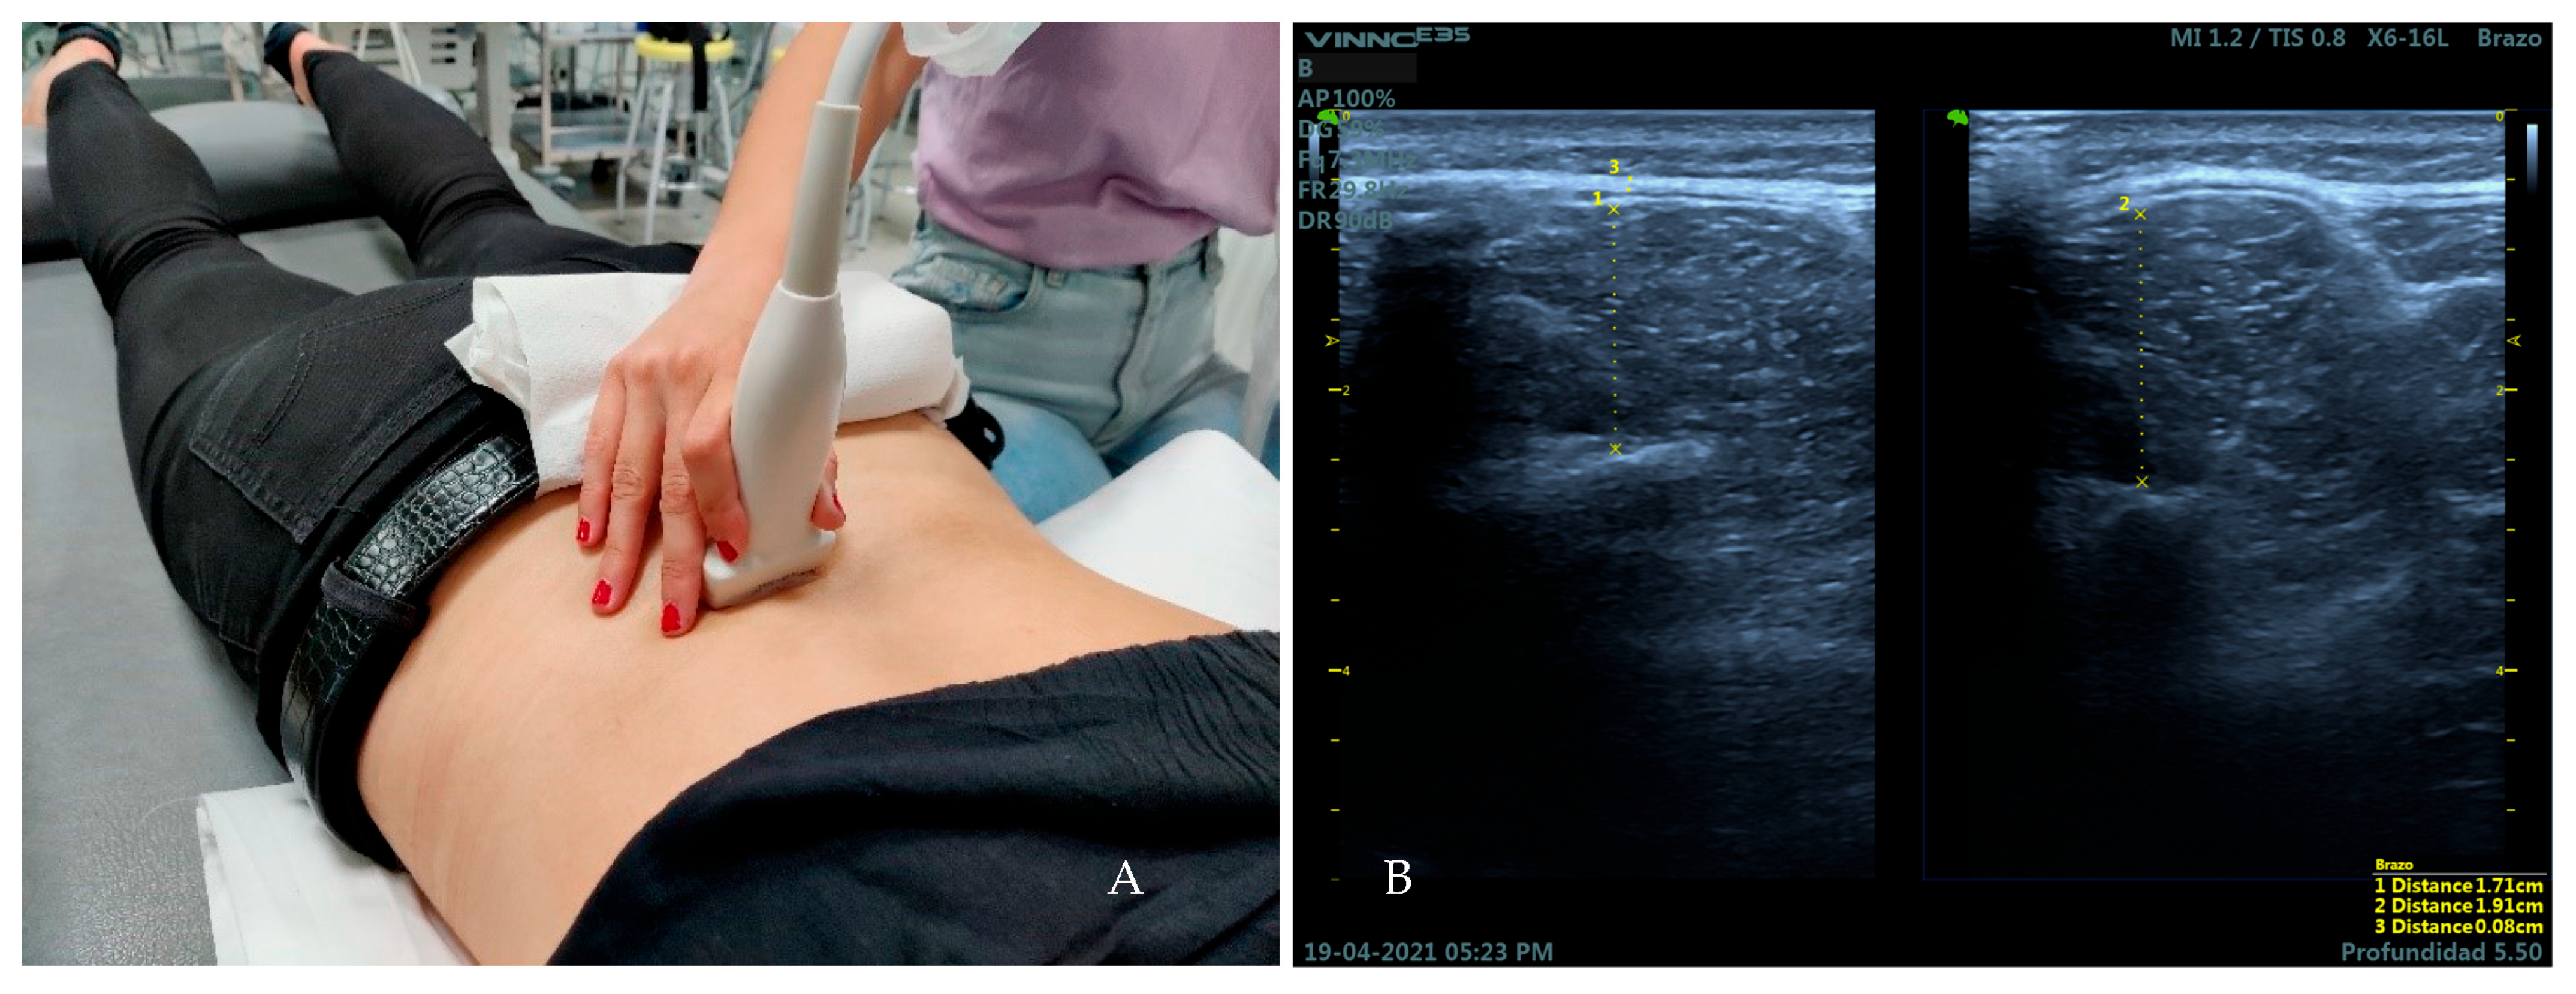

2.4. Measurement Instruments and Examiners

2.5. Measures